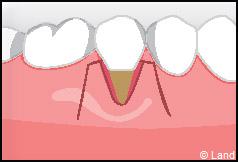

Elles font appel à des lambeaux de gencive restante à proximité des récessions, qui sont déplacés et repositionnés sur la récession.

LES TECHNIQUES AVEC APPORT DE GENCIVE OU « GREFFE DE GENCIVE » :

Elles font appel à un prélèvement sur le patient à un endroit où elle est en excès, qui est ensuite posé sur la récession.

Destinées aux zones esthétiques, elles consistent à prélever la partie profonde du palais (site donneur).